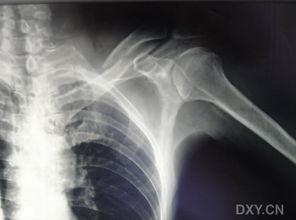

1. X光片上的“伤痕累累”:当你看到X光片上的锁骨,你会发现它就像被刀割过一样,断裂的地方清晰可见。